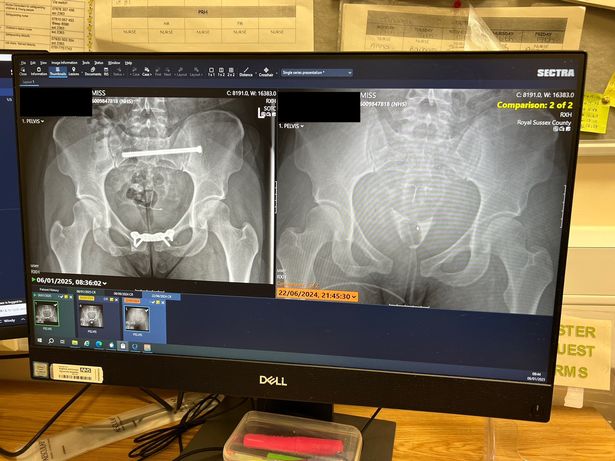

她的骨盆在车祸当天和七个月后受伤(图片:果酱媒体/ @mercedesthedancerxo)